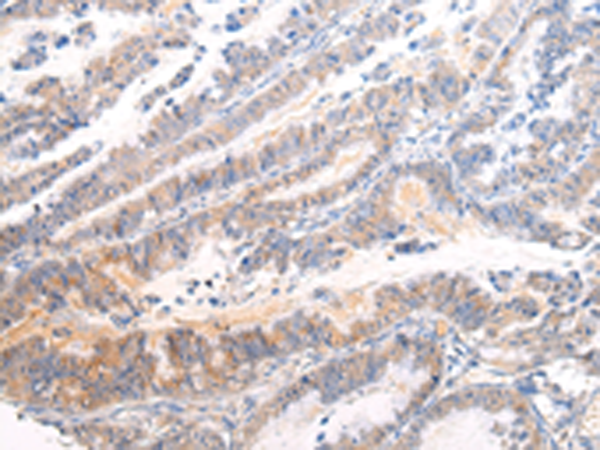

分类: 科研抗体货号: P12486别名: CDX3; CDX-3; CDX2/AS应用: WB,IHC反应种属: Human, Mouse